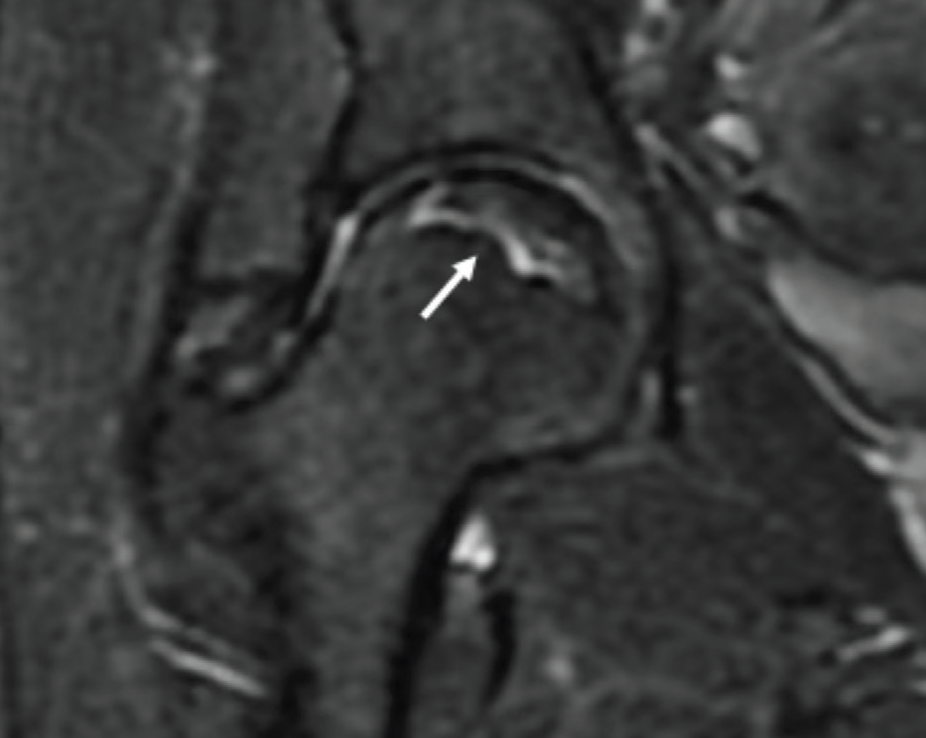

Femur Başı AVN

Devamı